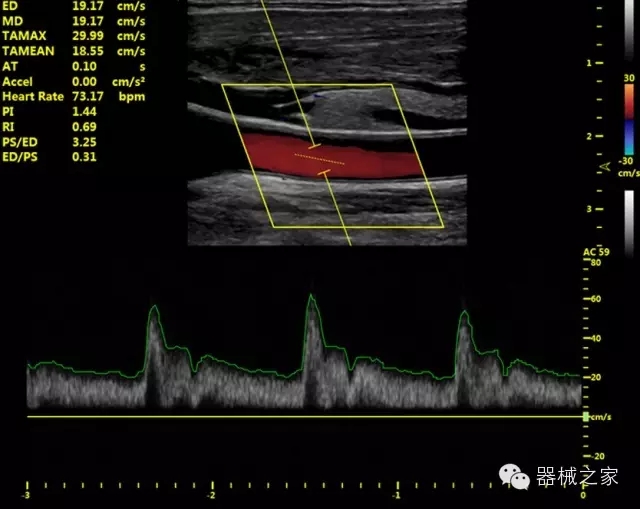

臨床圖片賞析

產(chǎn)品特點(diǎn)

·獨(dú)有的HoloTM PW 實(shí)時3取樣門PW成像技術(shù),精確進(jìn)行血管診斷;

·一鍵優(yōu)化B、Color、PW,Auto Doppler自動識別血管位置、偏轉(zhuǎn)角度等,提高工作效率;

·30°超廣角精細(xì)偏轉(zhuǎn)成像技術(shù),更優(yōu)異的頻譜圖像;